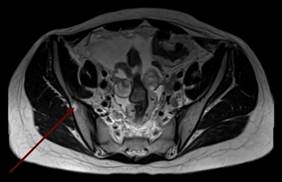

В дальнейшем была проведена МРТ органов малого таза с внутривенным контрастированием (рис. 3а, 3б). Было выявлено большое количество свободной жидкости, по задней поверхности брюшины и в пузырно-маточном углублении справа 2 узловых образования (канцероматоз), увеличенные лимфатические узлы во всех группах. Метастатические поражения костей таза.

Рис. 3а. Магнитно-резонансная томограмма органов малого таза с внутривенным контрастированием пациентки с раком желудка: метастатические поражения костей таза (1)